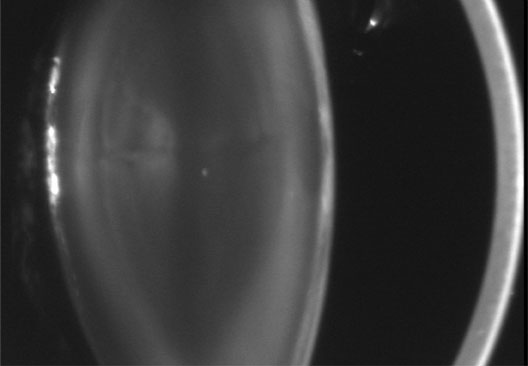

In general, patients with DM2 show less anticipation and a milder phenotype, and lack a congenital form. Affected individuals (DM1 and DM2) present with myotony and a characteristic pattern of weakness involving the facial, neck flexor, finger flexor, and hip girdle muscles. Severe arrhythmias or progressive cardiomyopathy may be fatal. Hypotestosteronism and oligospermia in males, and insulin insensitivity are frequent endocrinologic features. A specific set of serological changes is present, which includes low γ-globulin, elevated creatine kinase, and elevated follicle stimulating hormone (FSH) in males. In young adults, dust- and flake-like iridescent and highly refractile multicolored “needles” crisscross the anterior and posterior cortexes of the lens (the so-called “christmas-tree cataract”). The colors vary according to the angle of the incident light, and only a dim outline of the cataract is seen under retroillumination (Figs. 6 and 7). Under the scanning electron microscope the needles are smooth, rectangular, plate-like elements that are bordered by membranes and amorphous material, and run crisscross through the lens. The needles have a high sulfur content and pronounced S-S, CS-SC, and C-S vibrations under energy-dispersive x-ray and Raman microanalysis.34 They increase and accumulate with age, and may eventually result in a mature cataract. Rarely, macular and tapeto-retinal pigment epithelial degeneration, and optic atrophy are associated with DM.

Fig. 6. Christmas-tree cataract. Multiple small, irregularly sized opacities in the superior and posterior superficial cortex in a 43-year-old male patient with DM (Scheimpflug image).